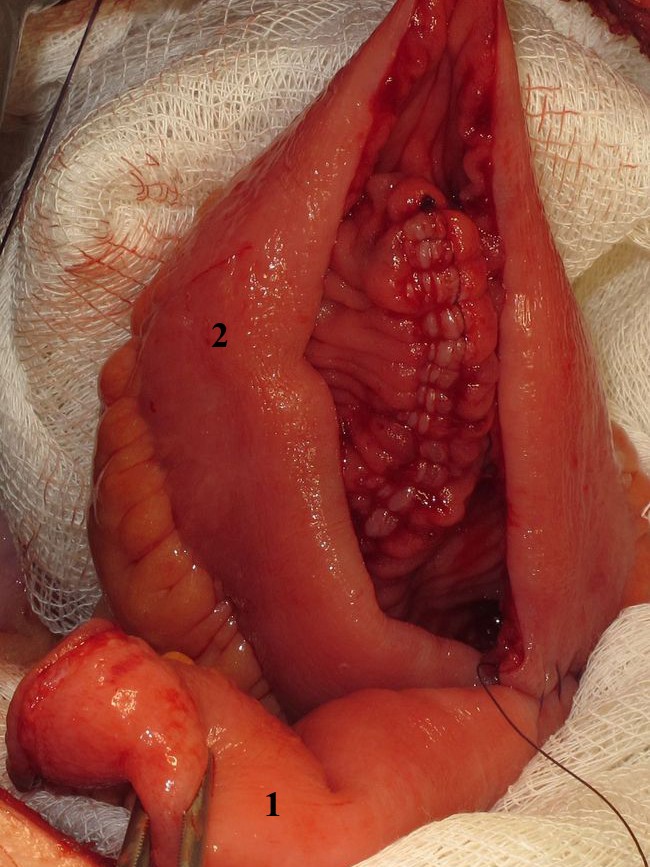

Операцию завершали восстановлением париетальной брюшины боковых стенок таза с размещением зоны мочеточнико-резервуарных анастомозов эктраперитонеально и дренированием брюшной полости через промежность двумя дренажами. Один (правый) размещали в зоне уретеро-илеоанастомозов (рис. 3, 4).

Рис. 3. Восстановление париетальной брюшины (А) с экстраперитонизацией зоны мочеточнико-резервуарного анастомозов (Б). В – дренажная система, установленная в зоне мочеточнико-резервуарного анастомозов. Г – наружные подвздошные сосуды